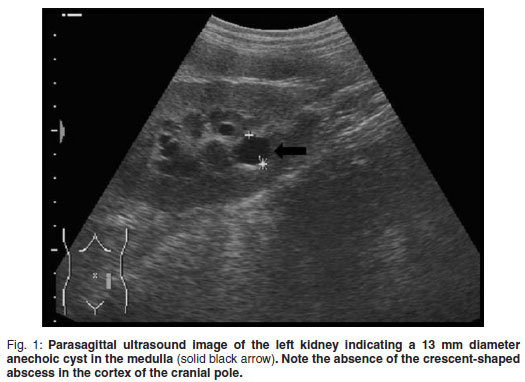

A 5-year-old, fawn, fully vaccinated, intact, male Boerboel weighing 58 kg was presented to the Onderstepoort Veterinary Academic Hospital (OVAH). The history suggested a change in the sexual behaviour of the dog with an increased tendency to 'mount' other dogs. Red discoloration of the urine for 2 weeks before presentation was noted. The only abnormalities that were seen on clinical examination were areas of echymoses on the penile mucosa. Faecal analysis was normal. Urine was collected via cystocentesis and analysed with the following findings: urine specific gravity (SG) 1.018, pH 7, proteins 1+, blood/haemoglobin 3+, erythrocytes 2+ and reticuloendothelial cells 1+. Abdominal ultrasound was performed using a Siemens Sonoline Omnia (Siemens AG, Erlangen, Germany) ultrasound machine and a mutli-frequency curvilinear array transducer operated at 5 MHz. This revealed multiple bilateral cystic structures measuring up to 13 mm in the medulla of the kidneys (Fig. 1). The prostate was normal in size with patchy hypo-to anechoic mottled areas. Bilaterally on the cranio-lateral aspect of the prostate there were more anechoic focal fluid accumulations up to 20 mm in diameter. The cytology of the ultrasoundguided fine-needle aspirates (FNA) was consistent with benign prostatic hyperplasia. Owing to financial constraints the owners declined further diagnostics and blood tests. The dog was castrated by the referring veterinarian.

Abdominal ultrasonography was performed under sedation using medetomidine (Domitor, Pfizer, 1 mg/kg) at a dose of 10 µg/kg intravenously. The left kidney measured 10×6×7.5 cm with a slightly uneven margin (cranial pole was larger). A small amount of hypoechoic subcapsular fluid surrounded the kidney. Multiple round, well-marginated, anechoic, cystic structures were seen mainly in the medulla with some extending into the cortex. The largest of these measured 2.5 × 1.5 × 2 cm. These cysts had a clear edge shadow, distal acoustic enhancement with a thin but clear hyperechoic far wall (Fig. 2a,b). Some cysts contained multiple internal hyperechoic specks. The renal cortex was normoechoic and the corticomedullary junction was distinct. Two of the cranial pole cysts of the kidney were more hypoechoic and communicated with a large 5×3×3cm hypoechoic well-marginated, crescentshaped mass which distorted the cranial pole of the kidney. This structure had hyperechoic septa and multiple hyperechoic internal specks that swirled on ballotment. Acoustic enhancement and edge shadowing were seen. Slice thickness artefact was noted in the mass mimicking sediment. No gas was noted in the mass. The right kidney measured 11 × 6 × 5 cm. Multiple smaller (largest about 1×1×1.5 cm) anechoic structures were present mainly in the medulla (Fig. 3a,b). Some of these cysts communicated with each other and some had multiple hyperechoic internal specks. No cysts were found in any of the other abdominal organs, including the pancreas and the liver. The ultrasonographic diagnosis was atypical multiple renal cysts with a suspected large left renal cranial pole cortical abscess. Other individual complicated cysts could not be excluded. The differential diagnosis for cyst-like structures included uniform blood clots, unclotted blood, abscesses without debris, lymphomatous masses and necrosis related to tumours or cystadenocarcinomas35.

Polycystic kidney disease has been diagnosed in the Persian cat and English bull terrier, West highland white terrier and Cairn terrier dogs4-7,12,32,33,36,3 and the cysts have been reported to originate from mainly the collecting duct and the distal part of the nephron17. The sensitivity and specificity for the detection of PKD in Persian cats at an age of 3 months using ultrasonography has been shown to be 92.6 % and 91 %, respectively8. Results were 100 % repeatable and disease progression was noted in 75 % of cats over a 1-year period45 but no data could be found for dogs. The disease also progressed in the case reported here with the cysts increasing in size from about 13 mm to 22 mm in diameter over a 2-year period. Although the disease in the current report presented much like PKD, potential cystic renal disease in related dogs was not investigated.